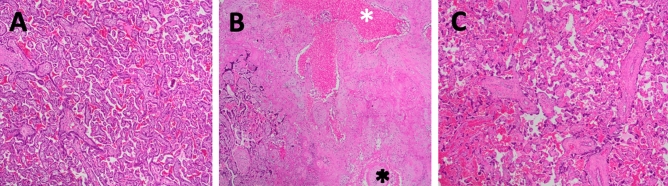

Placental histology

Placental pathology demonstrated increased frequency of microscopic (< 1.0 cm) infarctions and syncytial knots in placentas exposed to THC (4/5, p < 0.05) compared with none in controls (0/5) (Fig. 4). There was no histologic evidence of infection, increase in placental villi maturation or findings of chorangiosis. Placental weights were not different between treatment groups (Table 2).